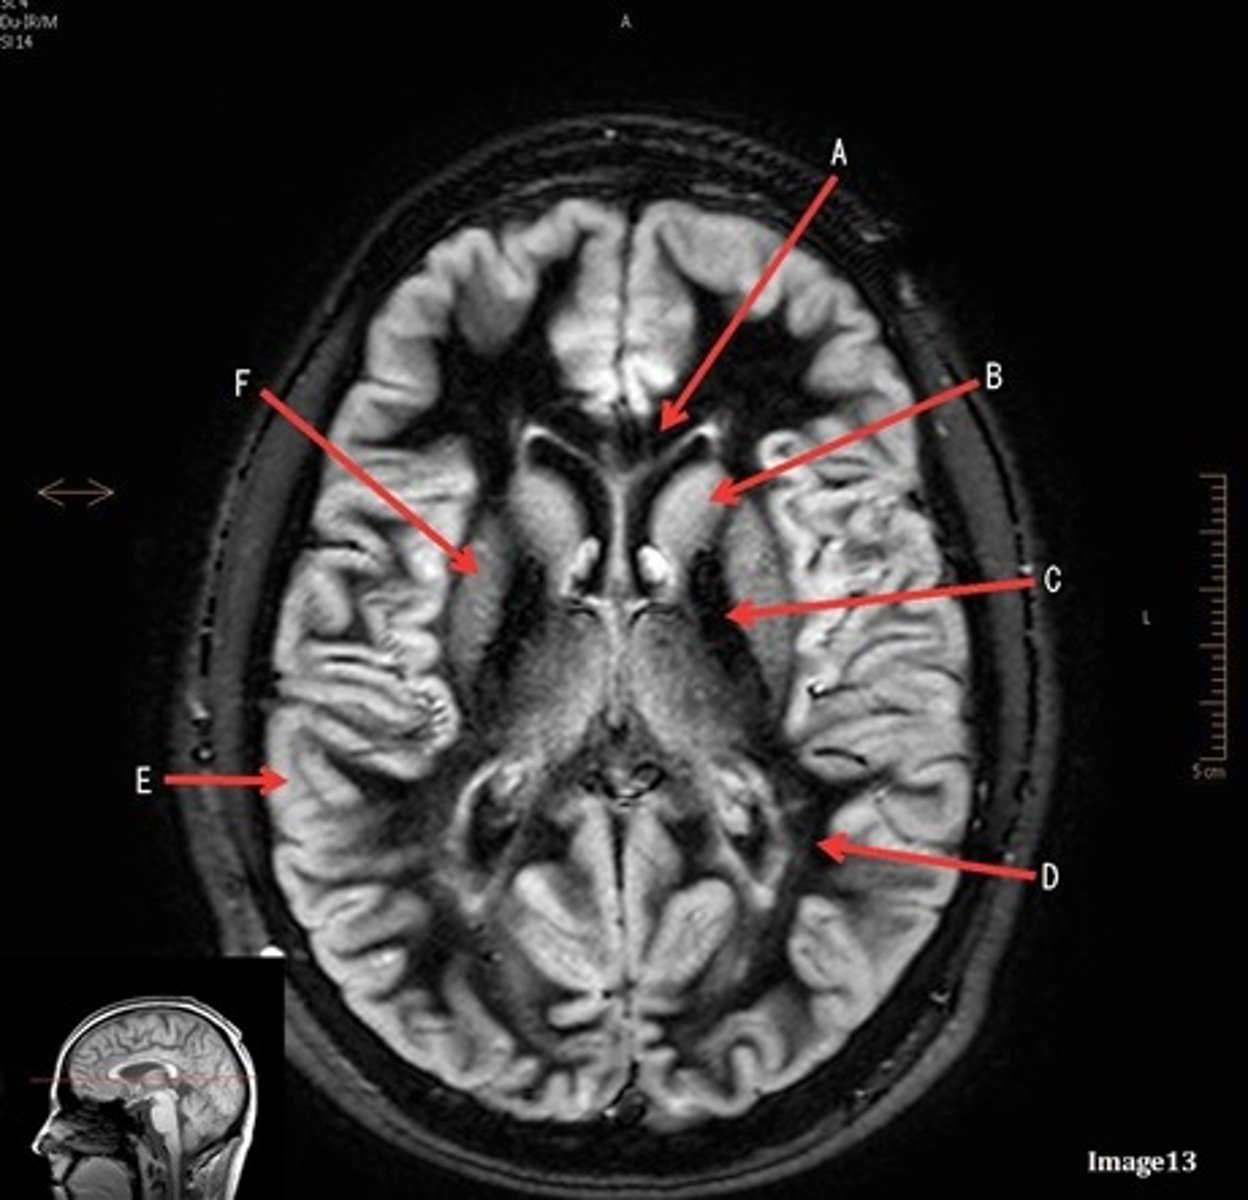

A (region)

dark band is called?

basal ganglia region

internal capsule

B

posterior horn of lateral ventricle

C

anterior horn of lateral ventricle

D

white matter

caudate nucleus

F

lentiform nucleus

E

gray matter

A

pituitary gland

lateral ventricle

corpus

fornix

internal carotid artery